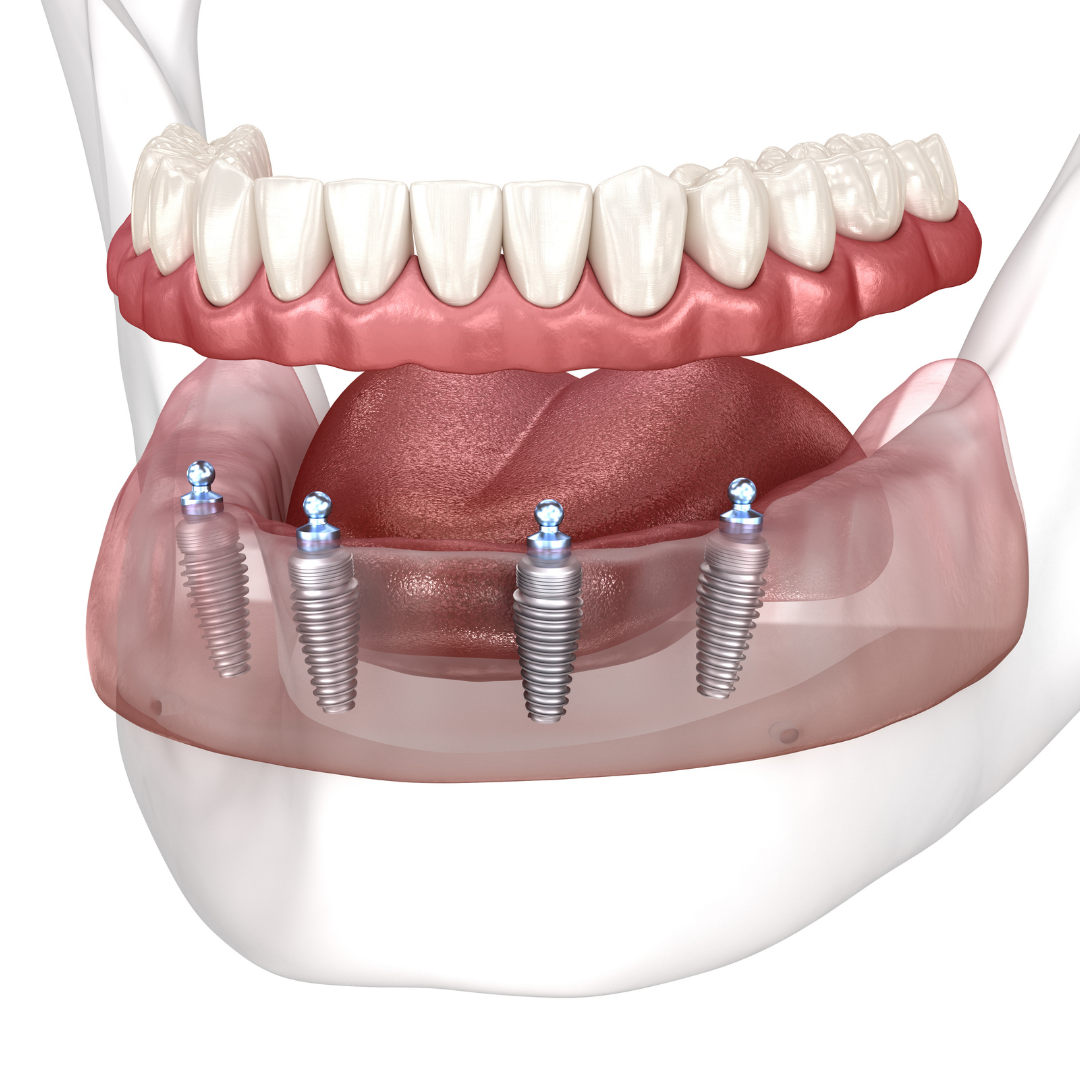

What are dental implants?

Learn how millions of Americans are replacing their teeth for life!

Patients no longer have to deal with low-quality temporary solutions like dentures, bridges, or partials. Dental implants are the new leading standard in tooth replacement options. They act and feel just like real teeth with an average lifespan of 20+ years.

Most traditional replacement solutions - like bridges or dentures - need to be replaced every 7 to 10 years resulting in hundreds of wasted dollars. Implants offer a long term solution for patients who want the best quality of life possible.

So, how do they work?

Every single dental implant consists of three parts - the implant, the abutment, & the crown. The implant is made of medical grade titanium. This part is surgically placed into the patient’s jaw bone and left to heal for 4-6 months afterwards.

This implant piece acts as the foundation for the rest of the tooth. Once the bone around the site has healed, the abutment and crown are placed on top of the implant. The end result is a beautiful, natural-looking new tooth!

Few people will ever be able to tell the difference between your implants and your real teeth.